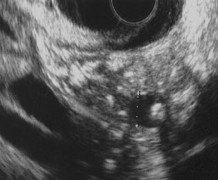

• Các hình ảnh tổn thương tụy trên siêu âm nội soi

Nốt tăng âm ở nhu mô tụy Dải tăng âm không có bóng lưng không có bóng lưng

Tổn thương dạng tổ ong Dày thành ống tụy chính

Thành ống tụy chính không đều Sỏi ống tụy chính

Hình 2.8. Các hình ảnh viêm tụy mạn trên siêu âm nội soi (Nguồn: Catalano M.F., Gastrointestinal Endoscopy, 2009; Yamabe A, Journal of Gastrointestinal and Digestive System, 2013) [31], [141].